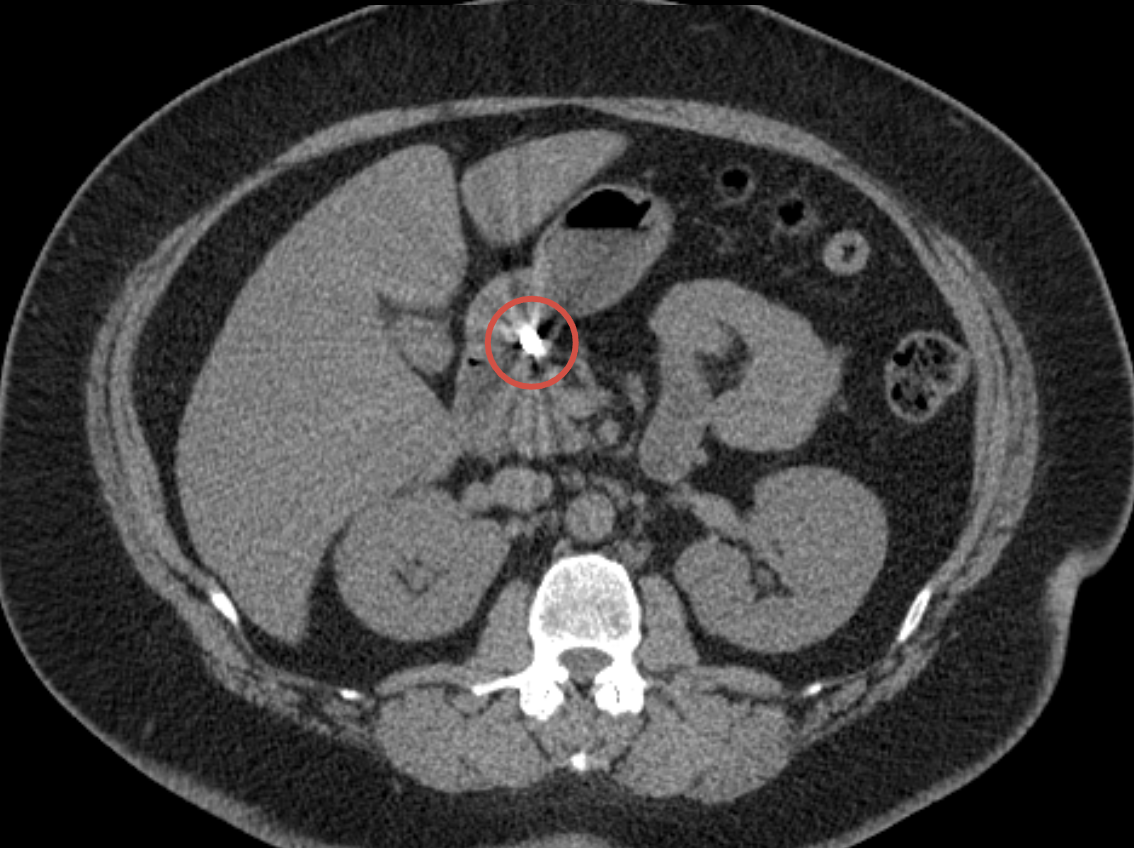

Иллюстрации к случаю:

1. КТ органов брюшной полости в день поступления — инородное тело в желудке.